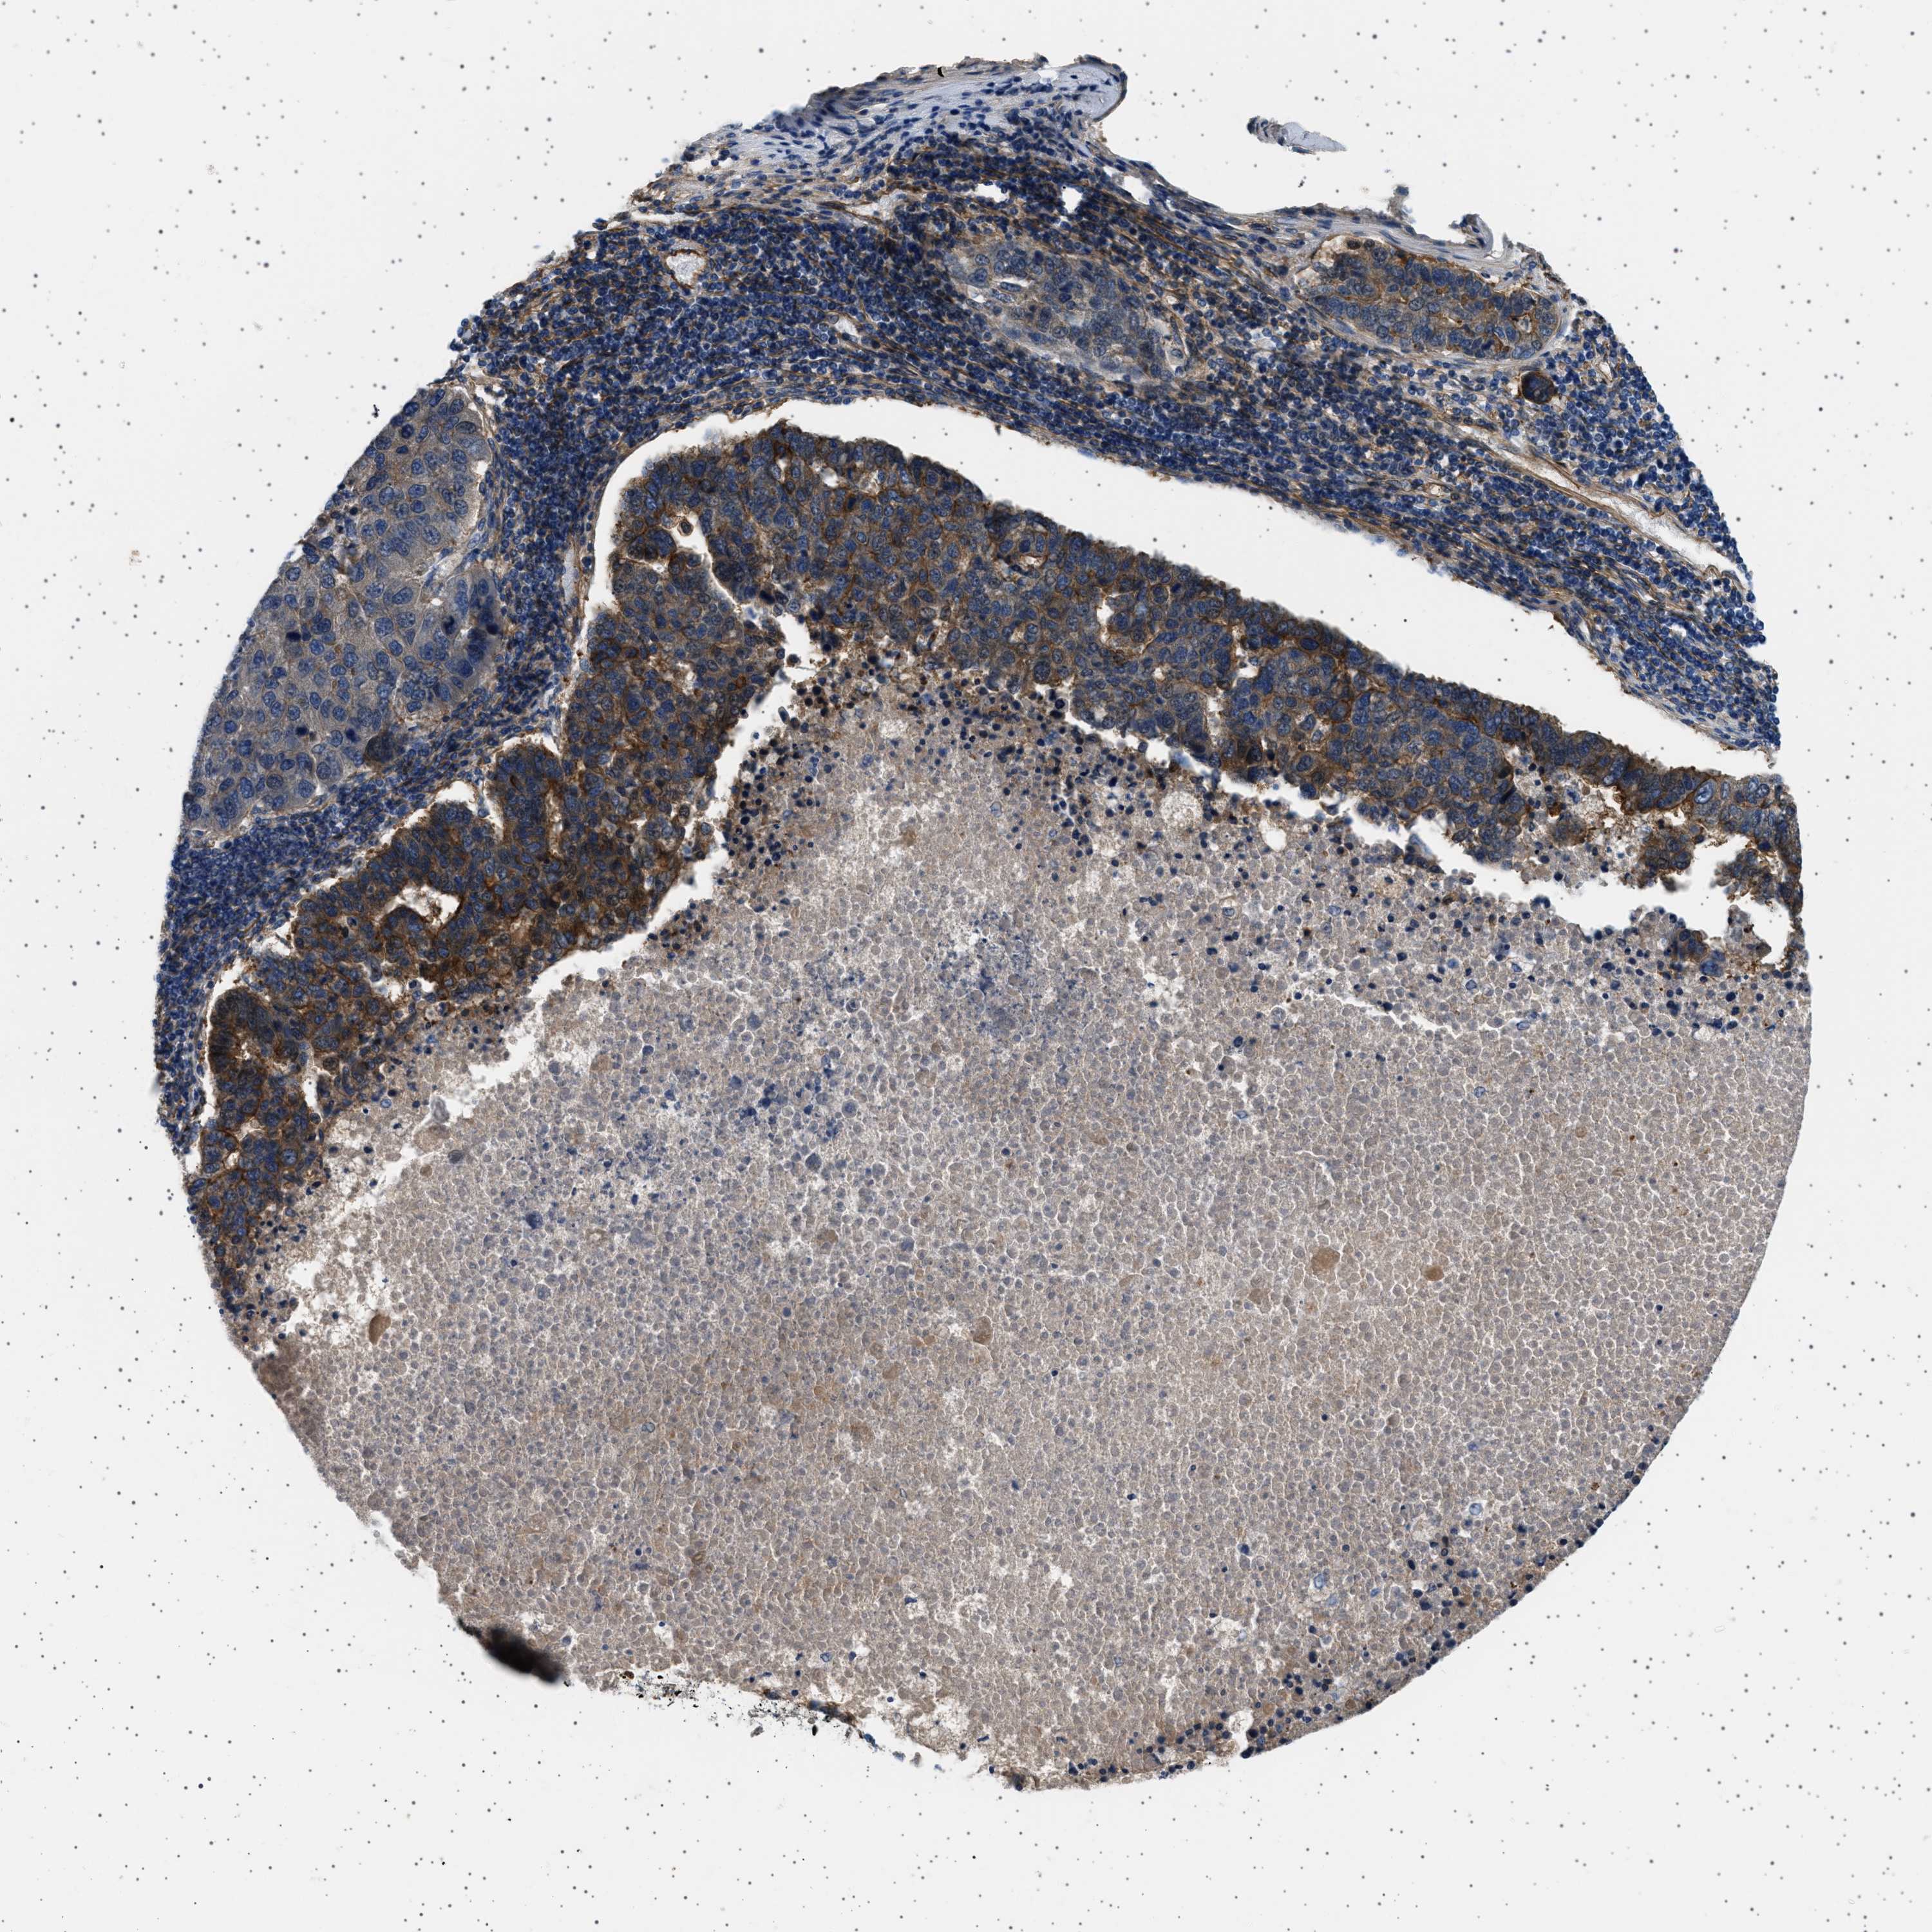

PANCREATIC CANCER - Protein expressioni

A mouse-over function shows sample information and annotation data. Click on an image to view it in a full screen mode. Samples can be filtered based on level of antibody staining by selecting one or several of the following categories: high, medium, low and not detected. The assay and annotation is described here.

Note that samples used for immunohistochemistry by the Human Protein Atlas do not correspond to samples in the TCGA dataset.

Antibody stainingi

Antibody staining in the annotated cell types in the current human tissue is reported as not detected, low, medium, or high, based on conventional immunohistochemistry profiling in selected tissues. This score is based on the combination of the staining intensity and fraction of stained cells.

Each image is clickable and will lead to virtual microscopy that enables deeper exploration of all samples and also displays staining intensity scores, fraction scores and subcellular localization as well as patient and tissue information for each sample.

Antibody HPA018096

Staining

High

Medium

Low

Not detected

Intensity

Strong

Moderate

Weak

Negative

Quantity

>75%

75%-25%

<25%

None

Location

Nuclear

Cytoplasmic/membranous

Cytoplasmic/membranous,nuclear

Adenocarcinoma, NOS